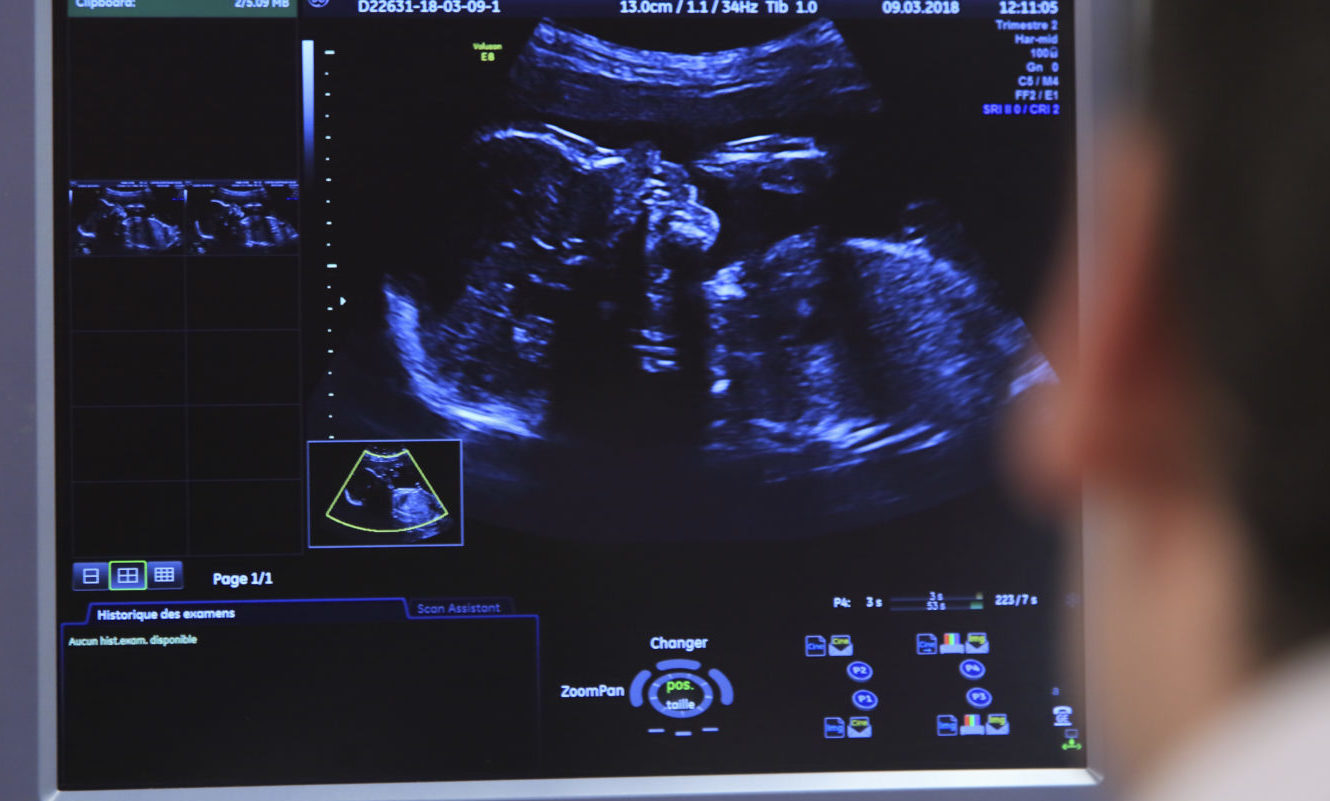

A méhlepény a magzat számára káros anyagokat alapvetően megszűri, a mikrószemcsék mégis áthatolhatnak rajtaFotó: AFP

Az emberi magzat már a méhlepényben is ki van téve a „támadásoknak” a brit természettudományos szakfolyóirat, a Nature oldalán közzétett írás szerint. A kutatók több placentát vizsgáltak meg nagy felbontású képalkotó eljárással, közülük öt volt koraszüléshez köthető, huszonhárom pedig nem.

Kiderült, hogy a légszennyező szénszemcsék bejuthatnak a méhlepény – magzat felőli – részébe is.

Mindegyik placentában szénrészecskékre bukkantak a méhlepény magzat felőli oldalán, a részecskék száma (átlagosan 20 ezer) attól függően változott, hogy mekkora légszennyezettséget szenvedett el a vizsgált alany.